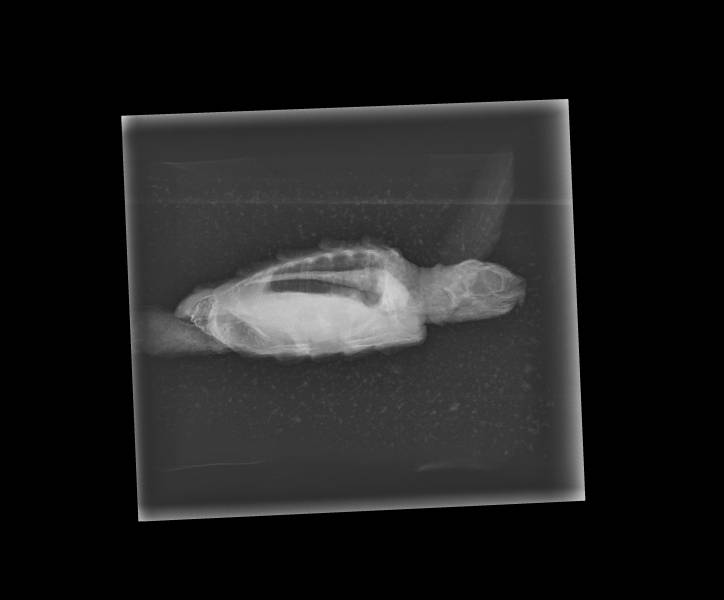

Medical - X-rays, bloods, regular health checks and specialized vets

X-rays allow us a window into our patients and are invaluable in directing the treatment we provide to our turtle patients. X-rays allow us to look into the internal structures (bones and organs) of our hatchlings following their arrival, with these x-rays acting as a baseline for ease of our team referring back to in order to see whether any changes are observed during their continued time in our care.